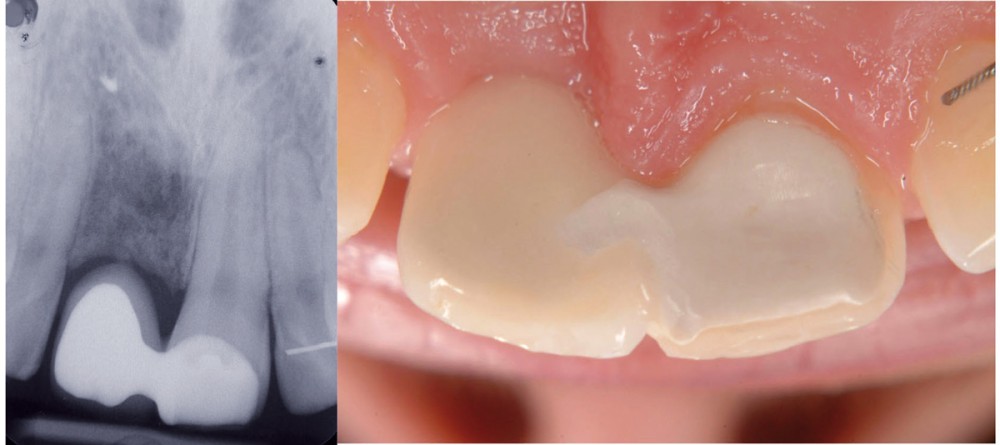

Avec l’avènement de l’implantologie et son développement rapide, il peut sembler difficile de laisser une place aux bridges collés lorsqu’il s’agit de remplacer une dent absente. Pourtant les contre-indications en implantologie (1, 2) sont assez nombreuses. Même en l’absence de ces contre-indications, il existe de nombreuses situations, notamment le remplacement de l’incisive latérale (3), où le bridge collé permet d’atteindre tous nos objectifs de traitement dans un rapport coût/bénéfice/sécurité très favorable. Par ailleurs, la conception de ces bridges collés évolue. Dans les descriptions classiques, le bridge collé est composé d’un intermédiaire et de 2 ailettes métalliques qui sont collées sur les faces linguales des 2 dents bordant l’édentement. Or, une analyse de la littérature internationale nous montre qu’il est possible, voire meilleur pour certains auteurs, de coller une seule ailette sur un pilier, solidarisée de l’intermédiaire (4). Il y a 9 ans (5), nous nous sommes intéressés à cette technique étonnante en commençant à traiter certains de nos patients en utilisant cette géométrie. Notre premier cas clinique illustrera nos propos.